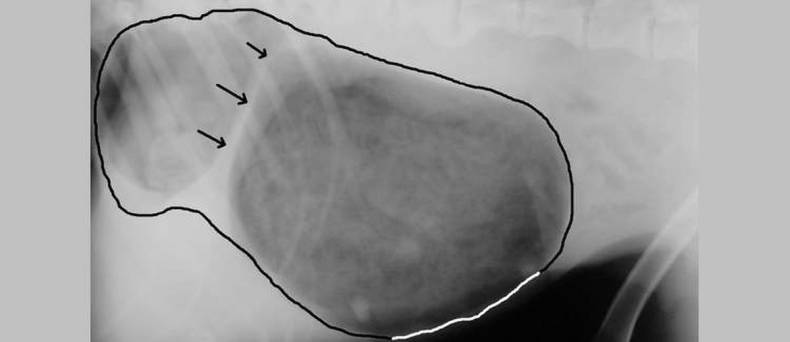

Als  de anaalzakken geïnfecteerd raken is het mogelijk dat er een pijnlijk abces ontstaat. Dit abces kan knappen met etterige uitvloei tot gevolg.

Als de anaalzakken te vol zijn, zal de dierenarts ze leeg gaan drukken. De vloeistof komt naar buiten en de nauwe doorgang wordt weer open gemaakt. Bij een infectie is antibiotica nodig. Een abces zal opengesneden worden. Als anaalklierontstekingen steeds terugkomen kan overwogen worden de anaalzakken weg te halen.